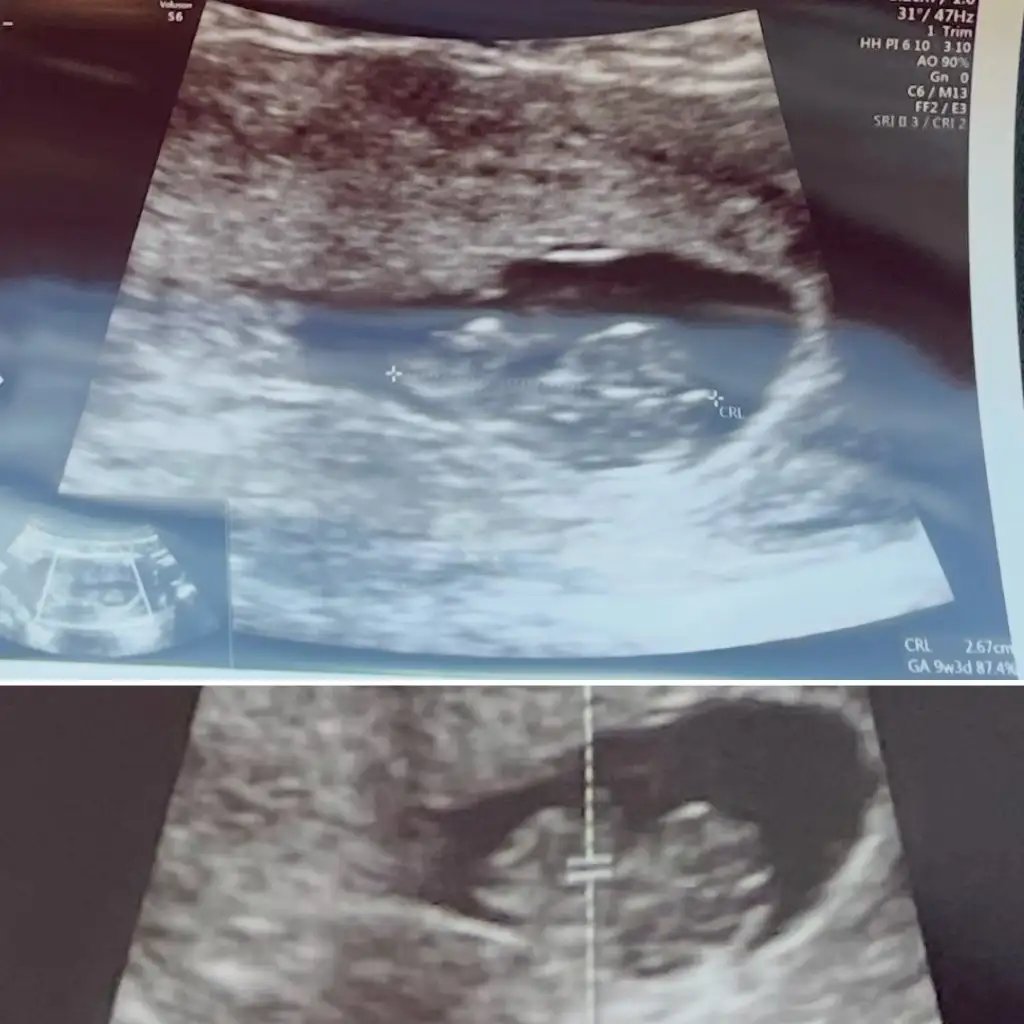

Kızlar ikiz bebişler bence bir kız bi erkek 🥰sizce